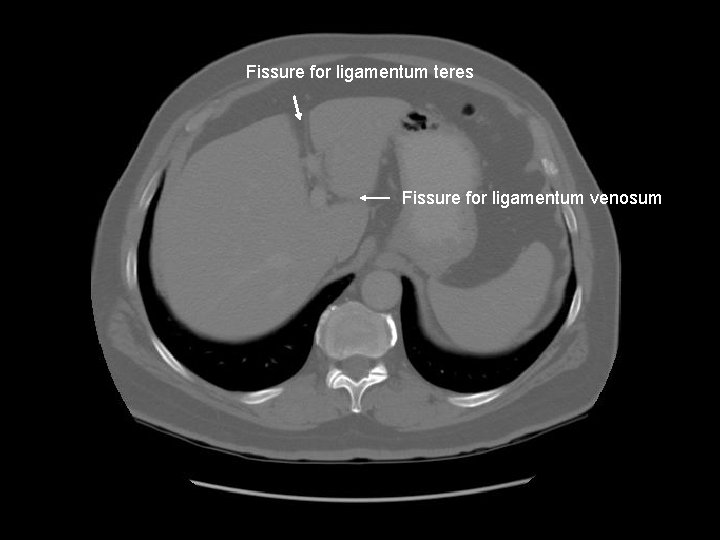

Fissure for ligamentum teres Fissure for ligamentum venosum

Caudate lobe Diaphragm